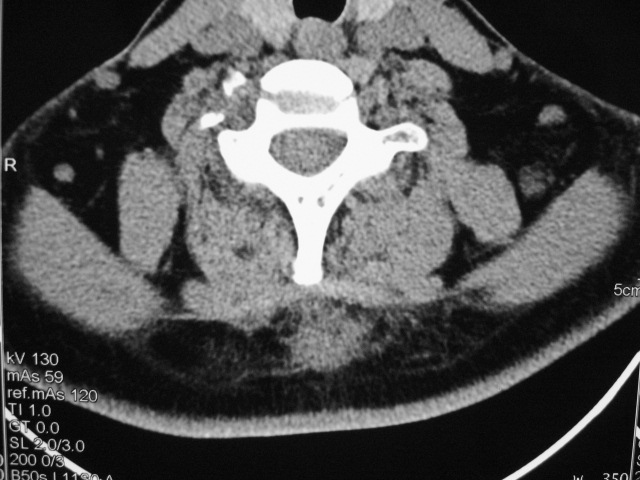

女,46岁,发现颈后区肿块3月余.

颈后软组织肿块,内可见坏死区及点状钙化,邻近颈椎棘突可见破坏,邻近肌间隙模糊,肿块周围脂肪间隙可见索条状影。

考虑:1)感染,结核可能;

2)肿瘤不能排除。